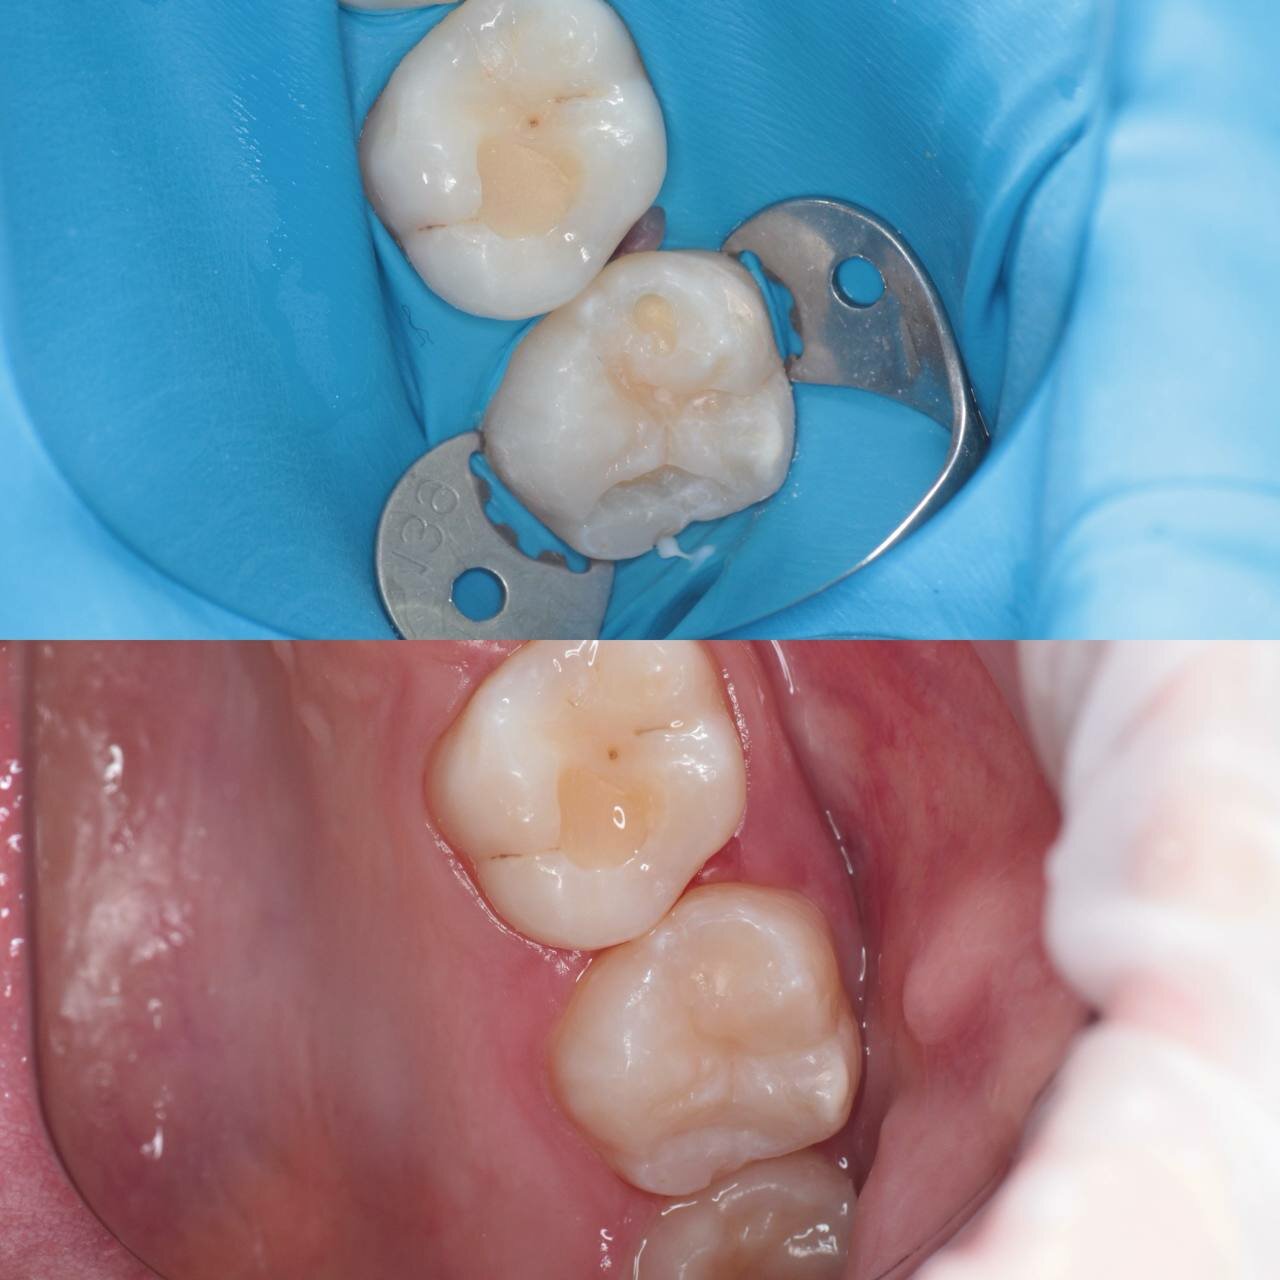

Gold Dent специализируется на различных направлениях стоматологии: общей терапии, хирургии, ортодонтии, эстетической и детской стоматологии, имплантологии, протезировании и эндодонтии. В клинике применяются передовые технологии, такие как цифровая стоматология CAD/CAM, лечение под микроскопом, компьютерная томография и костная пластика.

- Долговечные и эстетичные результаты (импланты, протезы).